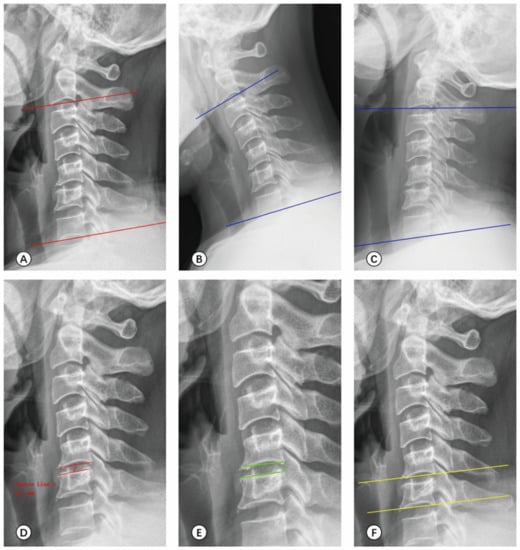

2.4.2. Radiological Measurement

3.4. Radiological Measurement

| Before | 12 Months After Surgery | Last Follow-Up | F | p | |

|---|---|---|---|---|---|

| C2-7 Cobb’s angle (°) | |||||

| UBE | 16.87 ± 2.89 *,† | 23.41 ± 4.04 * | 24.46 ± 3.94 † | 97.527 | <0.001 |

| PE | 16.66 ± 2.70 *,† | 22.38 ± 5.73 * | 23.53 ± 6.02 † | 39.525 | <0.001 |

| C2-7 ROM (°) | |||||

| UBE | 22.60 ± 7.59 *,† | 24.58 ± 9.58 *,‡ | 27.57 ± 9.45 †,‡ | 6.997 | 0.001 |

| PE | 22.08 ± 8.23 *,† | 25.71 ± 8.17 * | 26.42 ± 9.62 † | 4.500 | 0.013 |

| Intervertebral height of the surgical segment (mm) | |||||

| UBE | 5.51 ± 0.38 | 5.43 ± 0.42 | 5.52 ± 0.40 | 1.202 | 0.303 |

| PE | 5.42 ± 0.37 * | 5.61 ± 0.37 * | 5.56 ± 0.40 | 1.865 | 0.159 |

| Vertebral horizontal displacement of the surgical segment (mm) | |||||

| UBE | 1.24 ± 0.28 | 1.25 ± 0.29 | 1.32 ± 0.24 | 1.960 | 0.144 |

| PE | 1.21 ± 0.29 | 1.26 ± 0.29 | 1.20 ± 0.26 | 0.897 | 0.410 |

| Vertebral angular displacement of the surgical segment (°) | |||||

| UBE | 5.39 ± 1.16 | 5.55 ± 1.25 | 5.66 ± 1.20 | 1.276 | 0.282 |

| PE | 5.27 ± 1.34 | 5.39 ± 1.32 | 5.29 ± 1.29 | 0.125 | 0.883 |